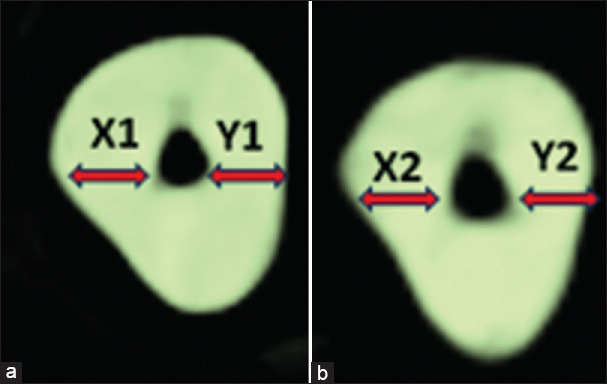

Methodology: This was an in vitro study where 40 extracted single-rooted single canal human premolar teeth were used. CBCT scans of all the teeth were taken before instrumentation and were randomly divided into four groups, with 10 samples in each; Group I-Protaper Next (PN), Group II-Protaper Gold (PG), Group III-Neo Endo Flex (NE), and Group IV-Gen Endo (GE). After cleaning and shaping, the canals with respective file systems postinstrumentation scans were performed, and the two scans were compared to determine canal transportation and centering ability at 3, 6, and 9 mm, from the apex.